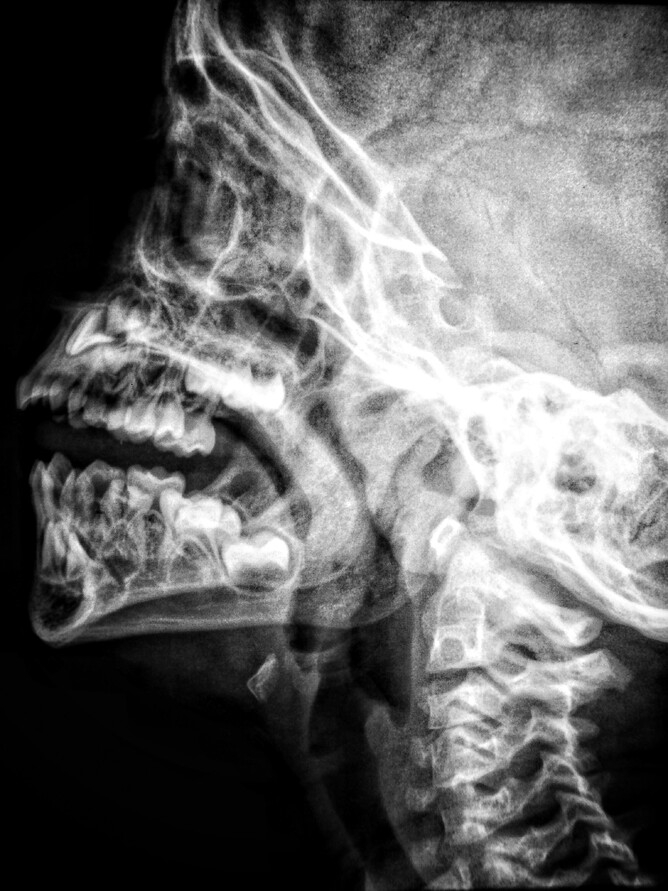

TMJ (Temporomandibular Joint) disorder is a common condition that affects the jaw joint and its surrounding muscles. Symptoms of TMJ disorder include pain and discomfort in the jaw, neck, and face, difficulty chewing, and clicking or popping sounds when opening and closing the mouth.